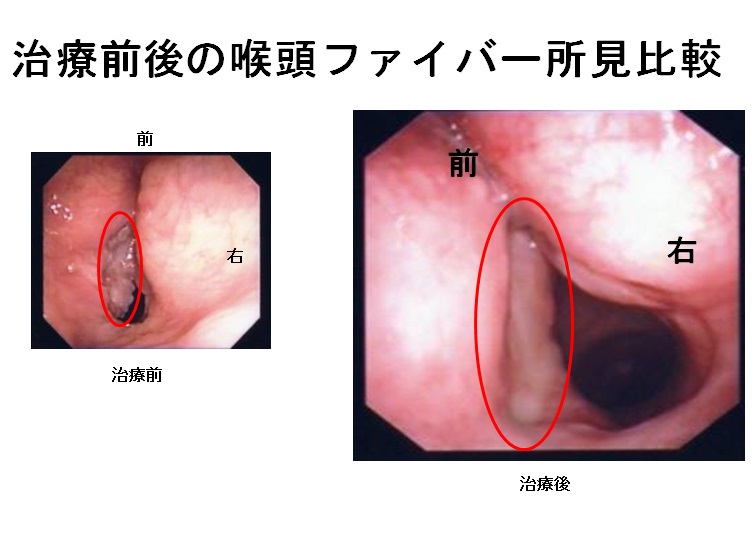

父の癌細胞が消滅したct Mri画像 難病 末期癌からの生還